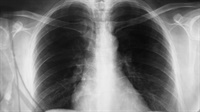

Dr. Cliff Tao will teach chiropractors the current imaging modalities, and technique for chest x-rays. He will help share what chiropractors should be looking for on chest x-rays, and often missed findings during x-ray readings. In this 2.5 hour webinar he will review:

Imaging Modalities for the Chest

XR Technique

Imaging Management of Chest Conditions